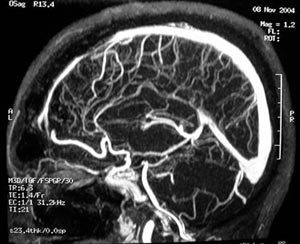

Figura 49 - Angiografia cerebral antes da cirurgia.

Figura 51 - Angio-ressonância cerebral realizada 5 dias após a cirurgia mostrando remoção total da lesão.